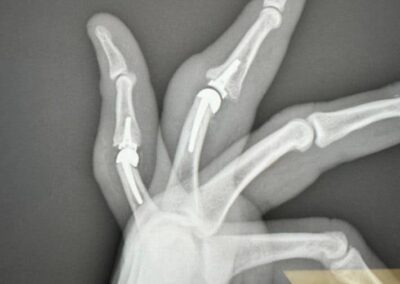

Finger Joint Arthritis and Joint Replacement Arthroplasty – Case 8

50 year old male with chronic post-traumatic arthritis with boutonniere deformities

The patient was reconstructed with Cobalt Chrome with Polyethylene cemented SR arthroplasty of ring and small finger PIP joints.

8 weeks post-operative result of PIP joint cemented SR arthroplasty of his left ring and small fingers.